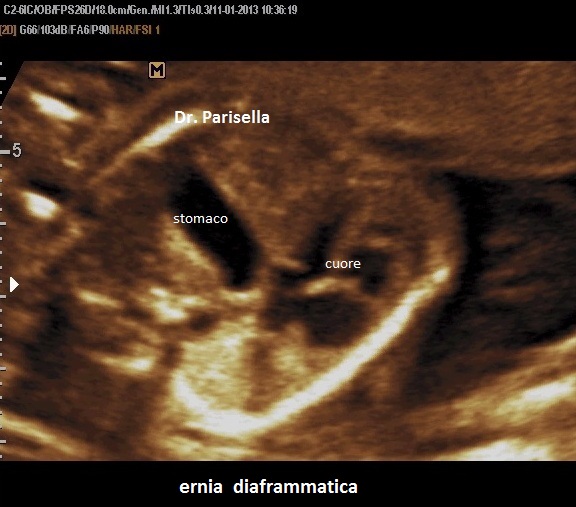

Ernia diaframmatica

La diagnosi si basa sulla evidenziazione ecografica di organi addominali nella cavitá toracica. Gli organi addominali passano in cavità toracica per il gradiente pressorio che viene a determinarsi tra cavità addominale (a maggiore pressione) e cavità toracica (a minore pressione).

L'ernia localizzata a sinistra può essere diagnosticata osservando nel torace la presenza dello stomaco o di anse di intestino e di uno  "shift" del cuore a destra. In caso di ostruzione intestinale si osserva polidramnios che compare raramente prima della 24a settimana e comporta una prognosi negativa perchè si associa a ipoplasia polmonare.